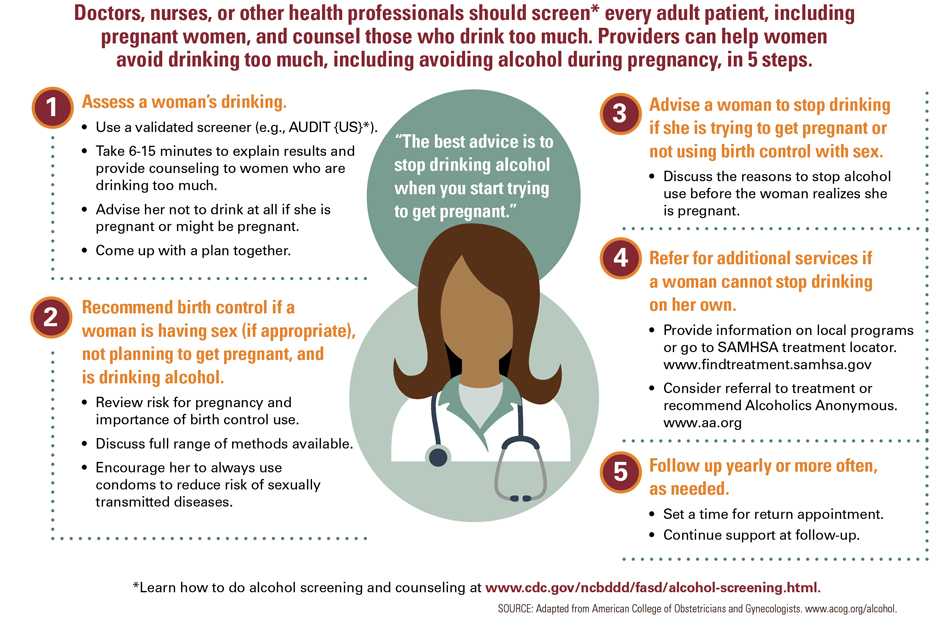

Doctors, nurses, or other health professionals can help prevent alcohol use during pregnancy in 5 ways:

- Provide alcohol screening and brief counseling to all women.

- Recommend birth control to women who are having sex (if appropriate), not planning to get pregnant, and drinking alcohol.

- Advise women who are trying to get pregnant to stop drinking alcohol.

- Refer for additional services for women who cannot stop drinking on their own.

- Follow up yearly or more often, as needed.